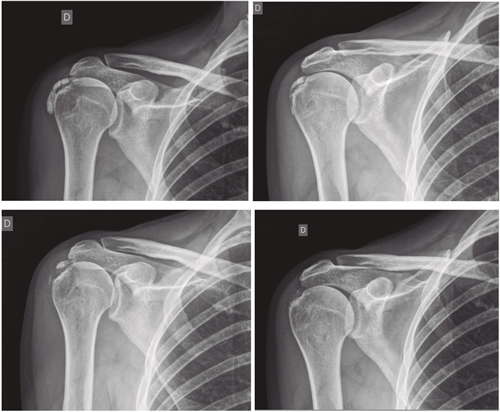

Fig. 4. Paciente mujer de 47 años con tendinitis calcificante de supraespinoso derecho, de tipo formativa, quien tras 30 sesiones de iontoforesis disminuyó el dolor medido por EVA de 6/10 a 3/10 y la calcificación de 38 mm a 8 mm (valoraciones al inicio, a las 10, a las 20 y a las 30 sesiones, respectivamente).